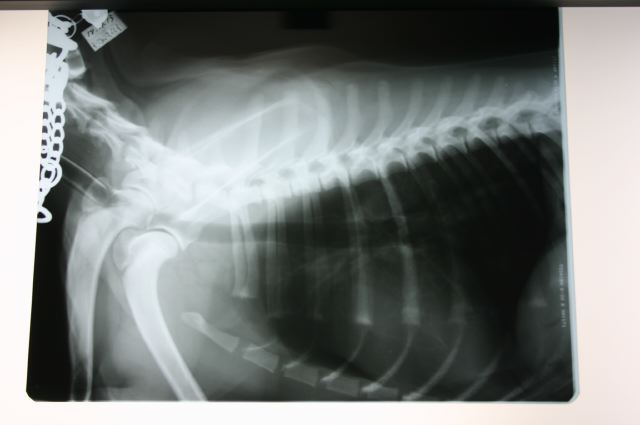

ついでと言ってはナンだけど、この機会にと思いお願いしてあった胸部と股関節のレントゲン、つめ切り、耳掃除、をしてもらう。

写真は

5枚目/滅菌布をとったところ。

感染予防の為、広範囲に毛が刈られ、手術用の高濃度のイソジンで丹念に消毒される。